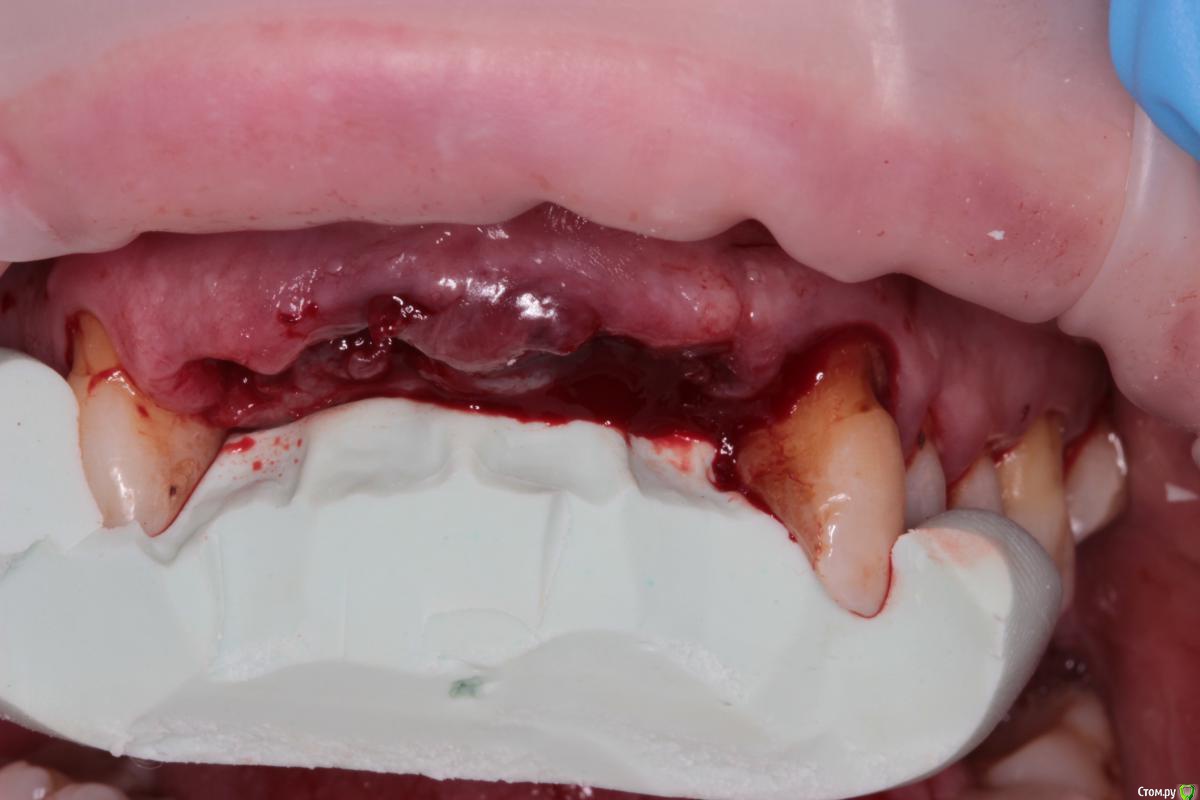

Abuk Опубликовано 27 ноября, 2015 Поделиться Опубликовано 27 ноября, 2015 (изменено) 1.bmp2.bmp3.bmp4.bmpЛечение.Альгинатные слепки,восковая моделировка.Удаление зубов и имплантата,удаление грануляций.Установка имплантатов,заполнение лунок графтом.сст,Времяхи по ключу. Изменено 27 ноября, 2015 пользователем Abuk 13 Ссылка на комментарий

bullbull Опубликовано 30 ноября, 2015 Поделиться Опубликовано 30 ноября, 2015 А что за винтик-красавЕц на 5-й фоточке? Ссылка на комментарий

Abuk Опубликовано 30 ноября, 2015 Автор Поделиться Опубликовано 30 ноября, 2015 А что за винтик-красавЕц на 5-й фоточке?Честно не знаю, лет пять назад ставила). Еще и кламера сделали на коронке. Столько смеялся когда увидел) Ссылка на комментарий